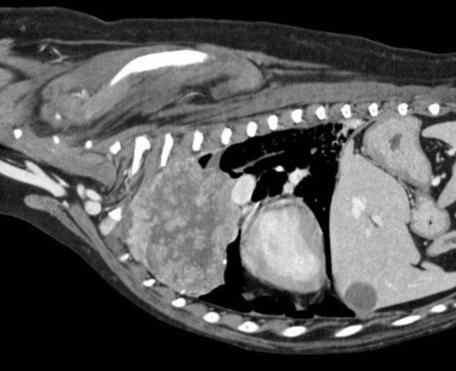

診斷過程通常需要多管齊下。獸醫可能會先聽診,然後建議做X光或超音波。X光是最基本的工具,可以看肺部的陰影變化。但如果腫瘤很小,X光可能看不出來,這時就需要進階檢查如CT掃描。

| 進階診斷 | CT掃描、活檢 | 確認腫瘤位置和類型 |